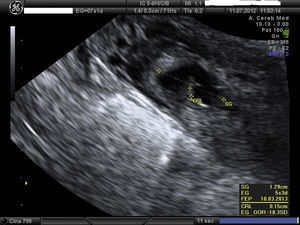

Embarazo actual de 7 semanas de amenorrea con sospecha de embarazo ectópico (EE) cornual. A la exploración, la paciente se encuentra estable, abdomen blando y depresible, sin signos de irritación peritoneal. Hemograma y bioquímica y coagulación normal y la β-HCG de 32.500mU/ml. Se confirma el diagnóstico de EE cornual derecho no accidentado por ecografía, presentando saco gestacional a nivel de cuerno derecho de 13mm con embrión de CRL 1,5mm y actividad cardíaca positiva (figs. 1 y 2). A la izquierda del saco, formación ecogénica mal delimitada de 18×18mm, muy vascularizada, compatible con trofoblasto (fig. 3). Anejos normales y no líquido libre.